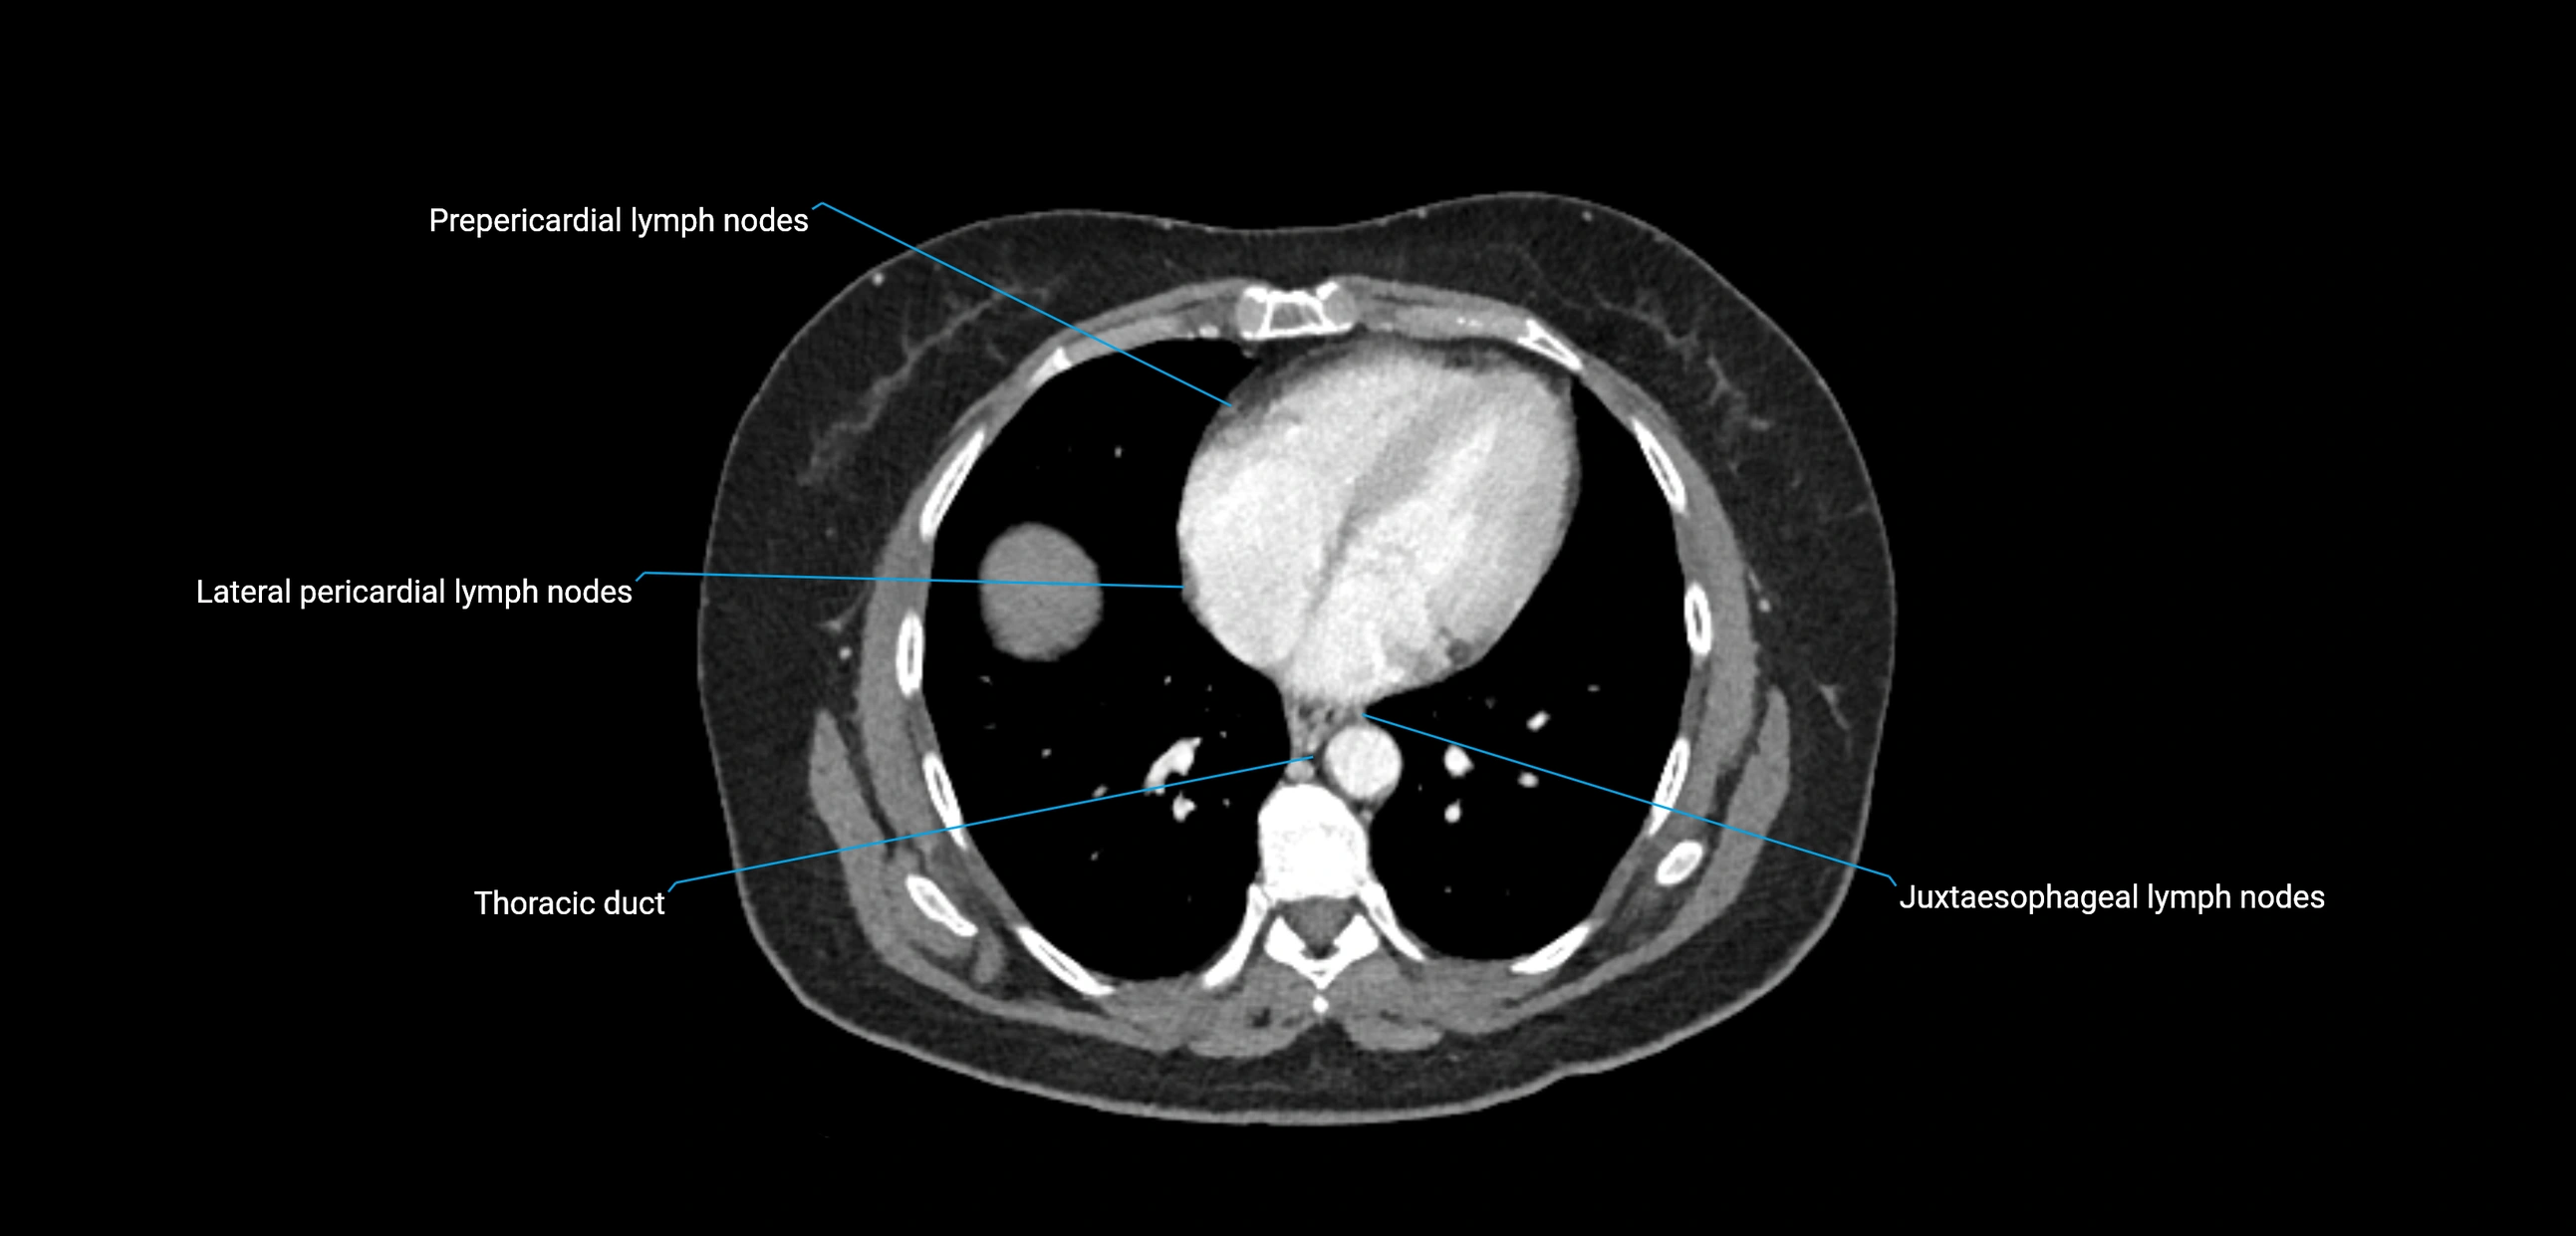

MRI images

image